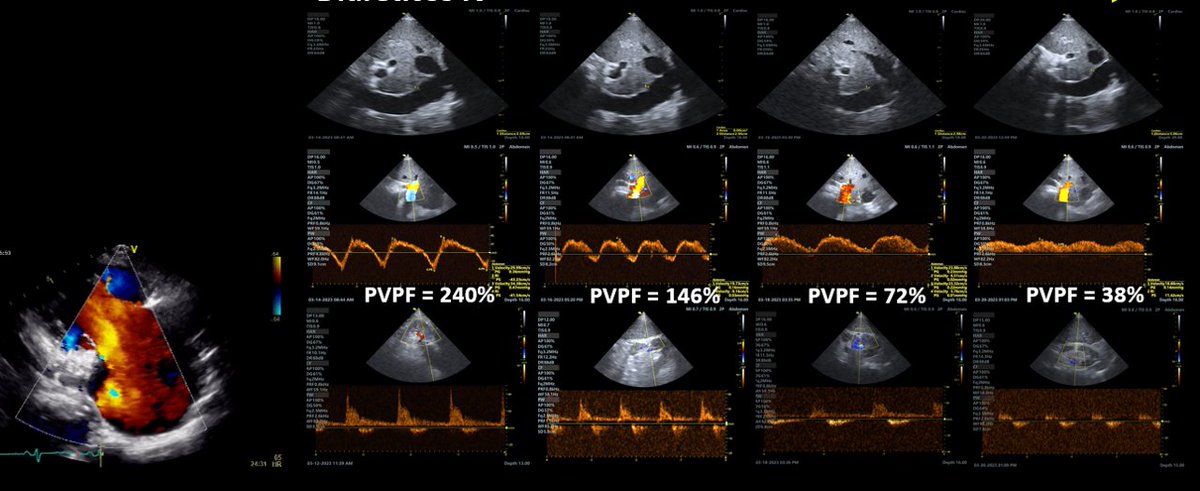

(6/x) So is the #VEXUS score in its purest form still valid? (i.e. the original paper by @WBeaubien @ThinkingCC et al.)

Conceptually, absolutely.

Do the exact thresholds and cutoffs used in the original scoring system apply perfectly to all populations? No.

VEXUS was derived and validated primarily in a cardiac surgical population, with increasing number of studies in other populations assessing and validating it.

With that said, however, the thresholds by which congestion cause organ dysfunction depend on the cause of the congestion.

For example, severe TR related congestion will always have an abnormal hepatic vein, however, with decongestion, portal vein pulsatility can normalize.

Similarly, PV pulsatility in pulmonary HTN patients does not typically normalize to less than 50% so normal for one of those patients could be >50% which traditionally would be severe congestion.

Credit to @ArgaizR for the diagram.